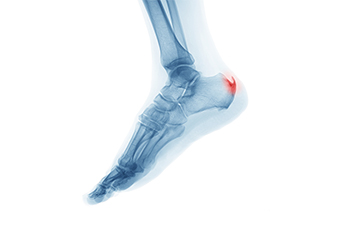

People who develop heel spurs often have heel and foot pain. A heel spur is defined as a bony growth that forms on the underside of the heel and is made of calcium. It can happen as a result of standing on hard surfaces for the majority of the day, or from consistently wearing shoes that do not fit correctly. The pain from a heel spur can range from a dull ache to a sharp pain, which may slightly diminish after walking. Some patients have found mild relief when specific stretches that target the heel are frequently performed. The plantar fascia, which attaches the heel to the toes is often affected in people who have heel spurs. This band of tissue may feel better when it is massaged, which can be done by standing on a tennis ball, and slowly rolling the foot back and forth. The calf stretch is also an effective stretch for the heel. This is done while standing on a step, and lowering one heel at a time until a gentle stretch is felt. If you have heel pain, it is suggested that you confer with a podiatrist who can effectively diagnose a heel spur, and offer you an appropriate treatment method.

Heel spurs are formed by calcium deposits on the back of the foot where the heel is. This can also be caused by small fragments of bone breaking off one section of the foot, attaching to the back of the foot. Heel spurs can also be bone growth on the back of the foot and may grow in the direction of the foot's arch.

Older individuals usually suffer from heel spurs and pain sometimes intensifies with age. One of the main conditions spurs are related to is plantar fasciitis.

Pain

The pain associated with spurs is often because of the weight placed on the feet. When someone is walking, their entire weight is concentrated on the feet. Bone spurs then have the tendency to affect other bones and tissues around the foot. As the pain continues, the feet will become tender and sensitive over time.

Heel pain is common and there are several causes. It can occur as a result of an injury or from wearing shoes that do not have adequate cushioning in the heel area. The foot condition known as plantar fasciitis can cause severe heel pain and a podiatrist is often consulted for relief. Additionally, enduring an Achilles tendon injury can also produce heel pain, and it can become difficult to walk. People who are afflicted with arthritis in the feet may have swollen heels and a reduced range of motion. For moderate heel pain, performing gentle stretches can help to strengthen the heel and it is helpful to avoid wearing high heels. A heel spur is a bony growth that forms on the bottom of the heel that causes heel pain, too. A heel spur can be diagnosed by having an X-ray taken to determine its size. If you have heel pain, it is strongly suggested that you are under the care of a podiatrist who can analyze the cause and offer you the correct treatment solutions.

Heel pain is often associated with plantar fasciitis. The plantar fascia is a band of tissues that extends along the bottom of the foot. A rip or tear in this ligament can cause inflammation of the tissue.

Heel spurs are another cause of pain. When the tissues of the plantar fascia undergo a great deal of stress, it can lead to ligament separation from the heel bone, causing heel spurs.